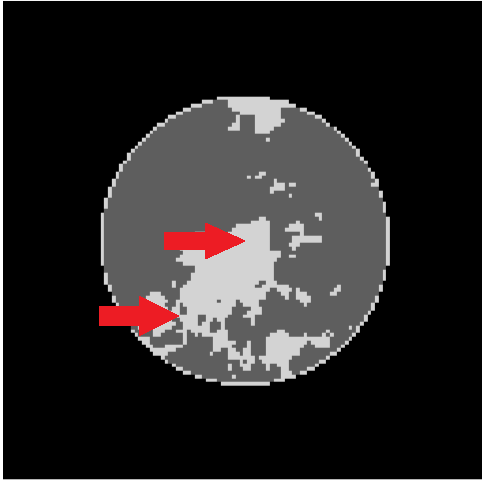

In order to evaluate we note that

| (25) |